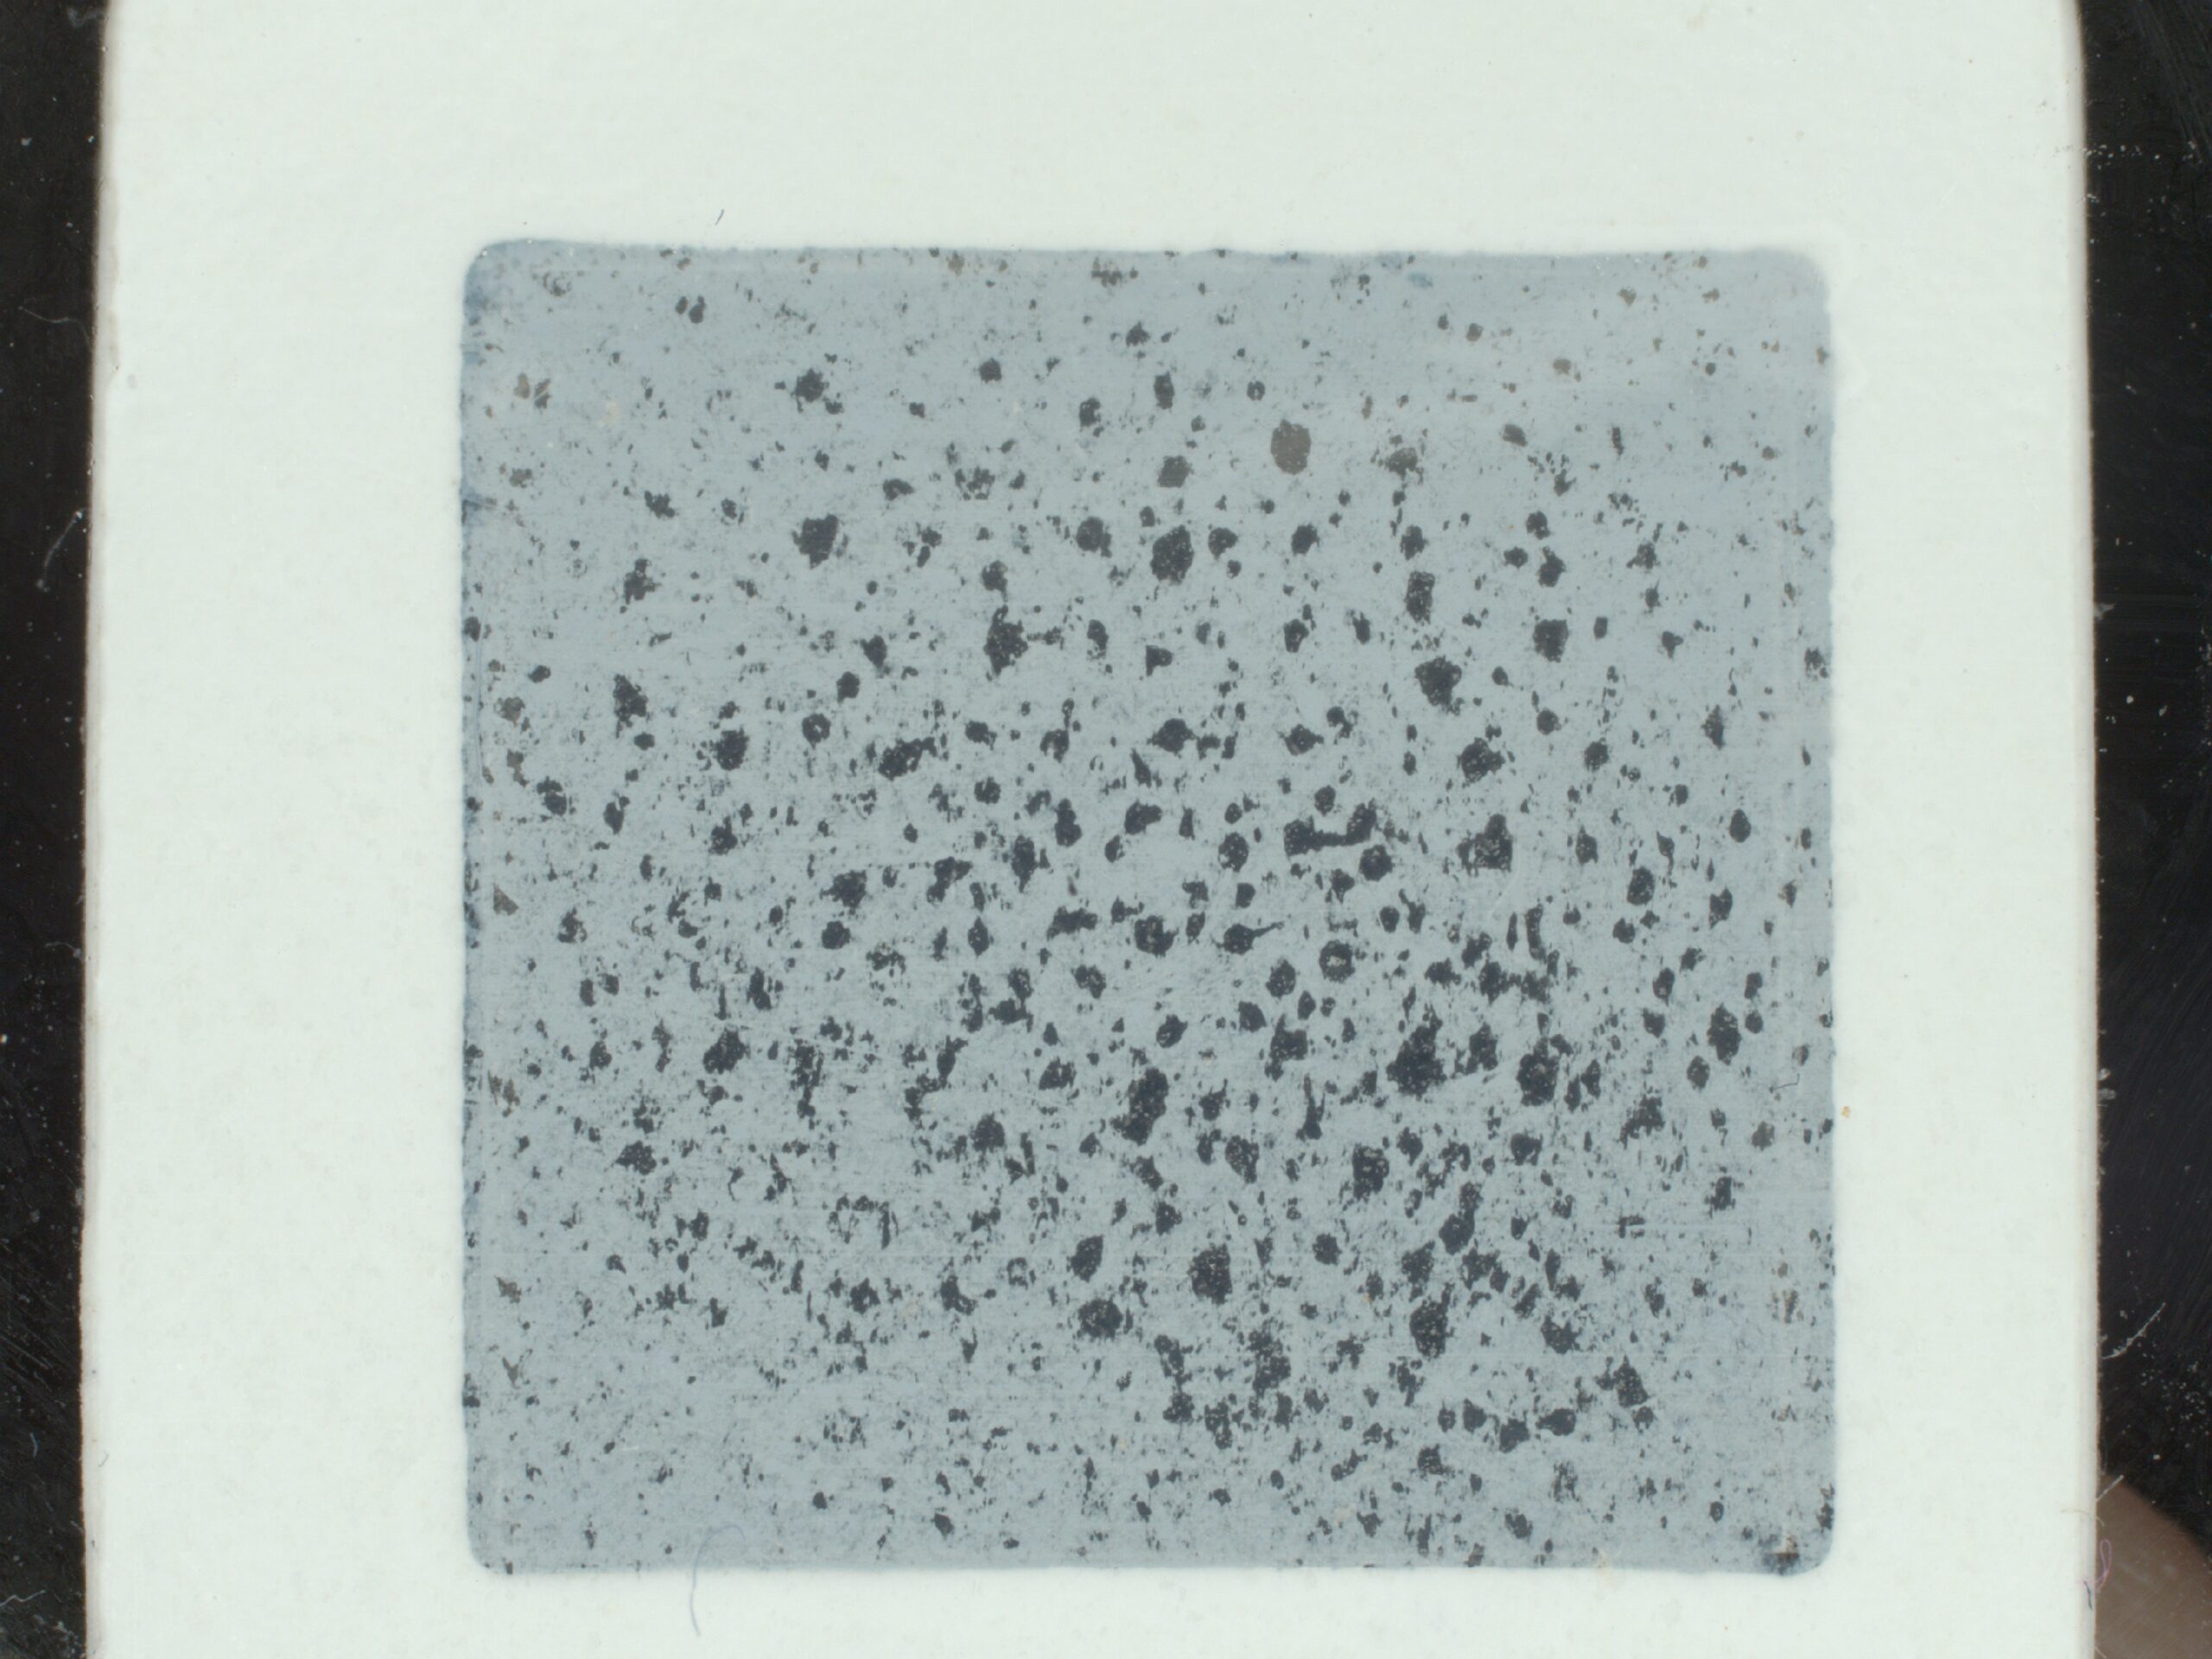

Mesure de sébum pour évaluer l’acné

Les peaux acnéiques ont tendance à produire une quantité de sébum plus élevée que la normale. De nombreux produits sont destinés à réguler la production de sébum.

Grâce au C-Cube et son lecteur de prélèvement, vous pouvez recueillir le sébum sur la peau et l’analyser. Étudiez ainsi les effets séborégulateurs de vos gammes.

La couleur de la zone d’échantillonnage est grise et uniforme, de manière à distinguer clairement les taches de sébum foncées. Les échantillons prélevés sur ces patchs sont analysés avec le lecteur d’échantillons Pixience et la caméra C-Cube de manière standardisée et systématique. L’analyse des niveaux d’intensité dans la zone de l’échantillon permet de déterminer un seuil entre le « fond » (la zone grise de l’échantillon) et l’intensité de la lumière « forme » (la zone noire, c’est-à-dire le sébum).

Il est ainsi facile de les distinguer et de mesurer la surface relative de sébum par rapport à la surface totale de la tache (exprimée en pourcentage de la surface totale).